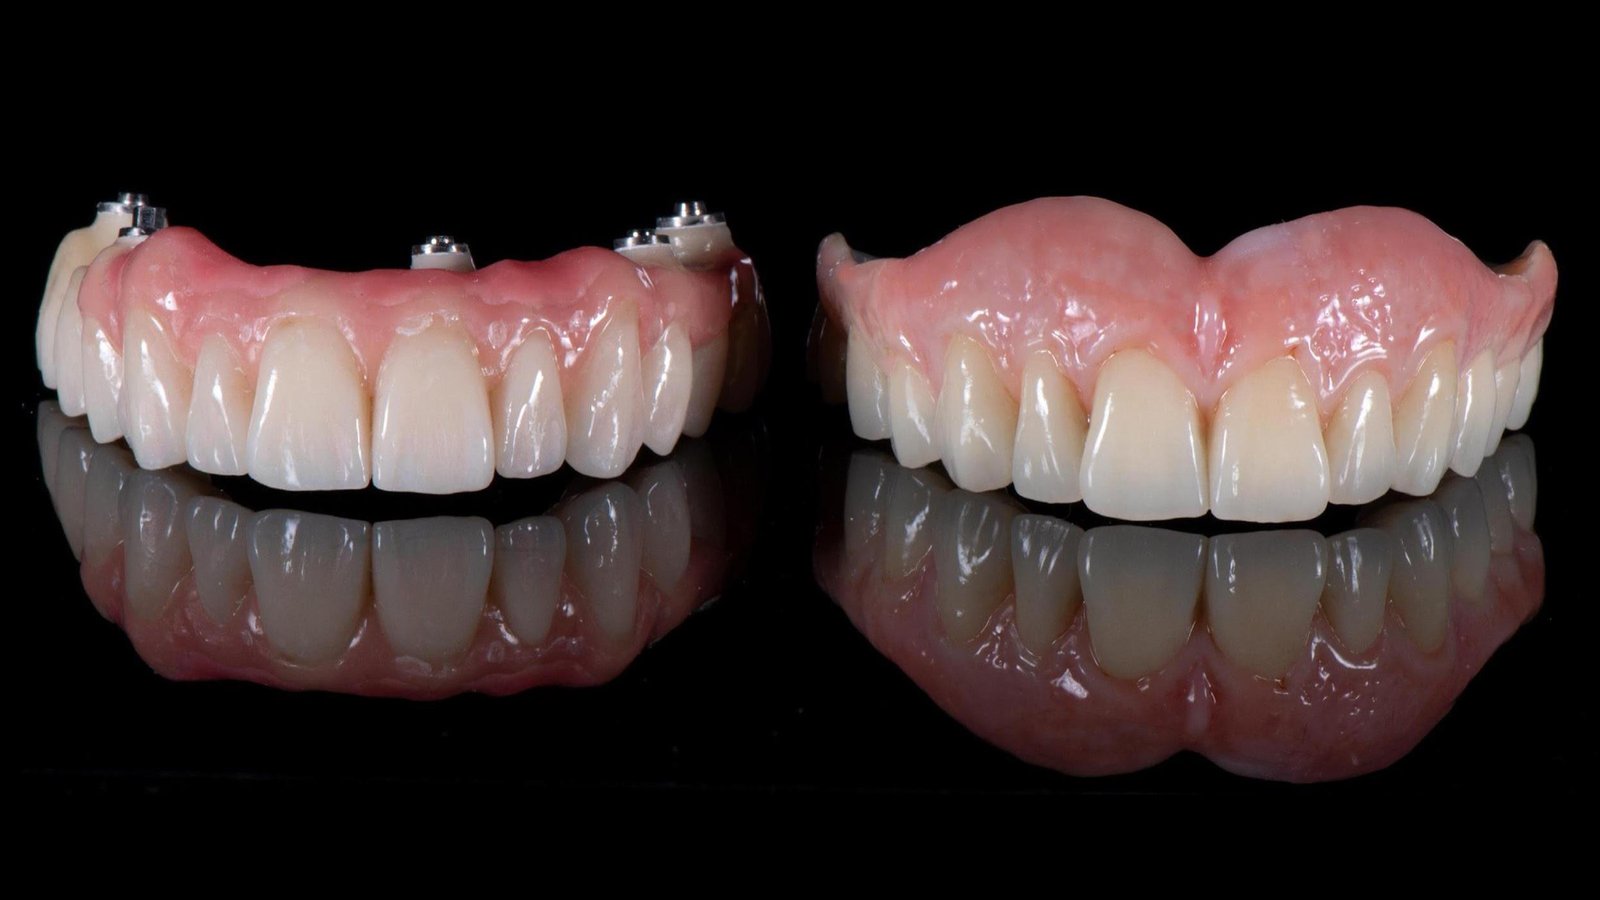

Αποτέλεσμα

Απολαύστε ξανά το φαγητό σας, όπως με τα δικά σας δόντια!